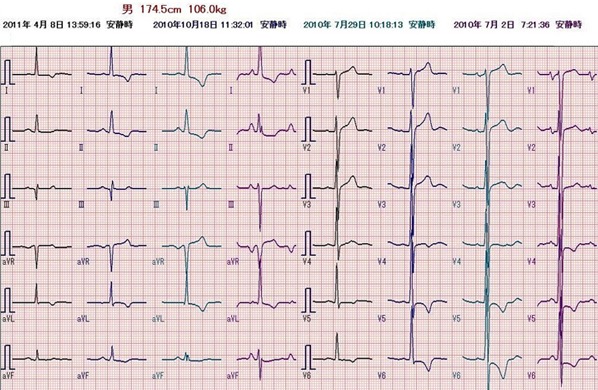

心電図

問題の心電図は洞頻脈、V1で典型的な左房負荷の所見を認め、左室の電位は高く、左室誘導(I、aVL、V5−6)でsagging型のST低下とT波の逆転を認める。典型的な圧負荷に対する左室肥大の所見である。左房負荷の存在から長期間の圧負荷と左心不全の存在が示唆される。来院時の身体所見は、血圧が高く頻脈。心臓では3音、4音がsummation gallopとして聴取されている。急性左心不全による肺水腫の状態である。胸部X線では、心陰影は拡大、左室の拡大と肺血管の再分布を認める。

以後、循環器科外来にて治療を継続。血圧は降圧剤により正常化し、病態は改善している。ほぼ10ヶ月後の胸部X線所見、心電図所見、心エコー検査所見は改善している。心電図の経時的変化をみると、STT変化は残存するが左房負荷と左室高電位は著明に軽減しているのが分かる。

10ヶ月後の心電図

心電図の経過